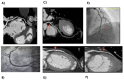

Early detection of asymptomatic coronary artery disease (CAD) is essential but underdeveloped. The aim of this study was to assess micro-RNA (miRNA) expression profiles in patients with or without CAD as selected by coronary CT angiography (CTA) and stratified by risk of CAD as determined by Framingham Risk Score (FRS). In this pilot study, patients were divided into two groups based on the presence or absence of CAD. Disease status was determined by Coronary CTA by identification of atherosclerosis and/or calcified plaque in coronary arteries. There were 16 control subjects and 16 subjects with documented CAD. Groups were then subdivided based on FRS. Pathway-specific microarray profiling of 86 genes using miRNAs isolated from whole peripheral blood was analyzed. MiRNA were differentially expressed in patients with and without CAD and who were stratified on the basis of FRS with miRNA associated with endothelial function, cardiomyocyte protection and inflammatory response (hsa-miR-17-5p, hsa-miR-21-5p, hsa-miR-210-3p, hsa-miR-29b-3p, hsa-miR-7-5p and hsa-miR-99a-5p) consistently upregulated by greater than twofold in groups with CAD. The present study reveals that miRNA expression patterns in whole blood as selected on the basis of coronary CTA and risk scores vary significantly depending on the subject phenotype. Thus, profiling miRNA may improve early detection of CAD.